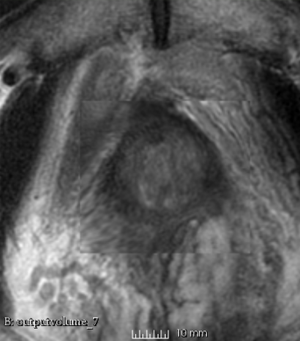

Case 7

Reference intraop volume

Reg Result Slicer 3.6 with ITKv3

Reg Result Slicer 4.4 with ITKv4

We used this sample data with Reader 1 segmentations to visually evaluate differences in the registration results. All three results of BRAINSFit with ITKv3 in Slicer 3.6 look reasonable. Using BRAINSFit with ITKv4 in Slicer 4.4 creates a reasonable result for Case 7, but look strongly distorted towards the edges of the bounding box in Case 8 and 9.